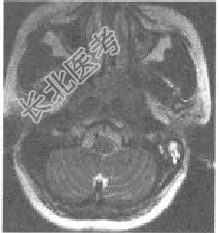

- [材料题] 患者,男性,53岁,发现鼻塞及左侧颈部包块、面部疼痛1个月余,查体左颈部有一质硬包块。MRI如下图所示:

- 简答题1、该患者最可能的诊断为?

- 简答题3、MRI在诊断鼻咽癌中的作用是什么?